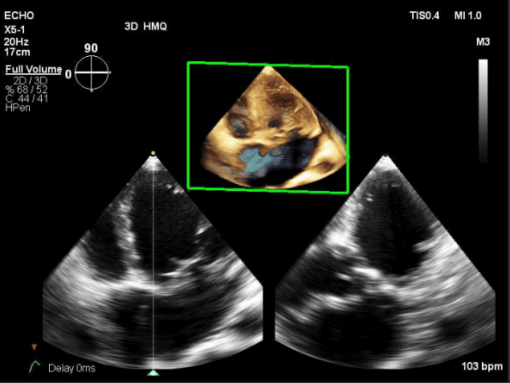

入院检查:甲状腺功能、凝血功能、血常规、hs-CRP均正常范围,eGFR 71ml/min/1.73㎡,BNP 3881.7pg/ml ,肝功能“TBIL 41.2umol/L DBIL 17.1 umol/L IBIL 24.1umol/L”;心电图提示“异位心律,心房颤动,偶发室早,QRS 波宽度113ms”;心超提示“扩张型心肌病 ,全心扩大(左房内径 64mm,左心室舒张末期内径82.1mm),左室壁运动弥漫性减低,二尖瓣中度反流,三尖瓣轻度反流,主动脉瓣轻-中度反流,心律失常,左室收缩功能减低(LVEF 37%)”;心肌MR提示“扩张型心肌病,全心扩大,LVEF 22.4%,左心室基底段-中央段间隔壁心肌中层见点、线样延迟强化”;动态心电图“心房颤动24小时总心搏114767次,平均90次/分,最慢67次/分,最快164次/分,多源室早(1918次,包括单发室早1854次,成对28对,短阵室速2阵)”。

超声心动图